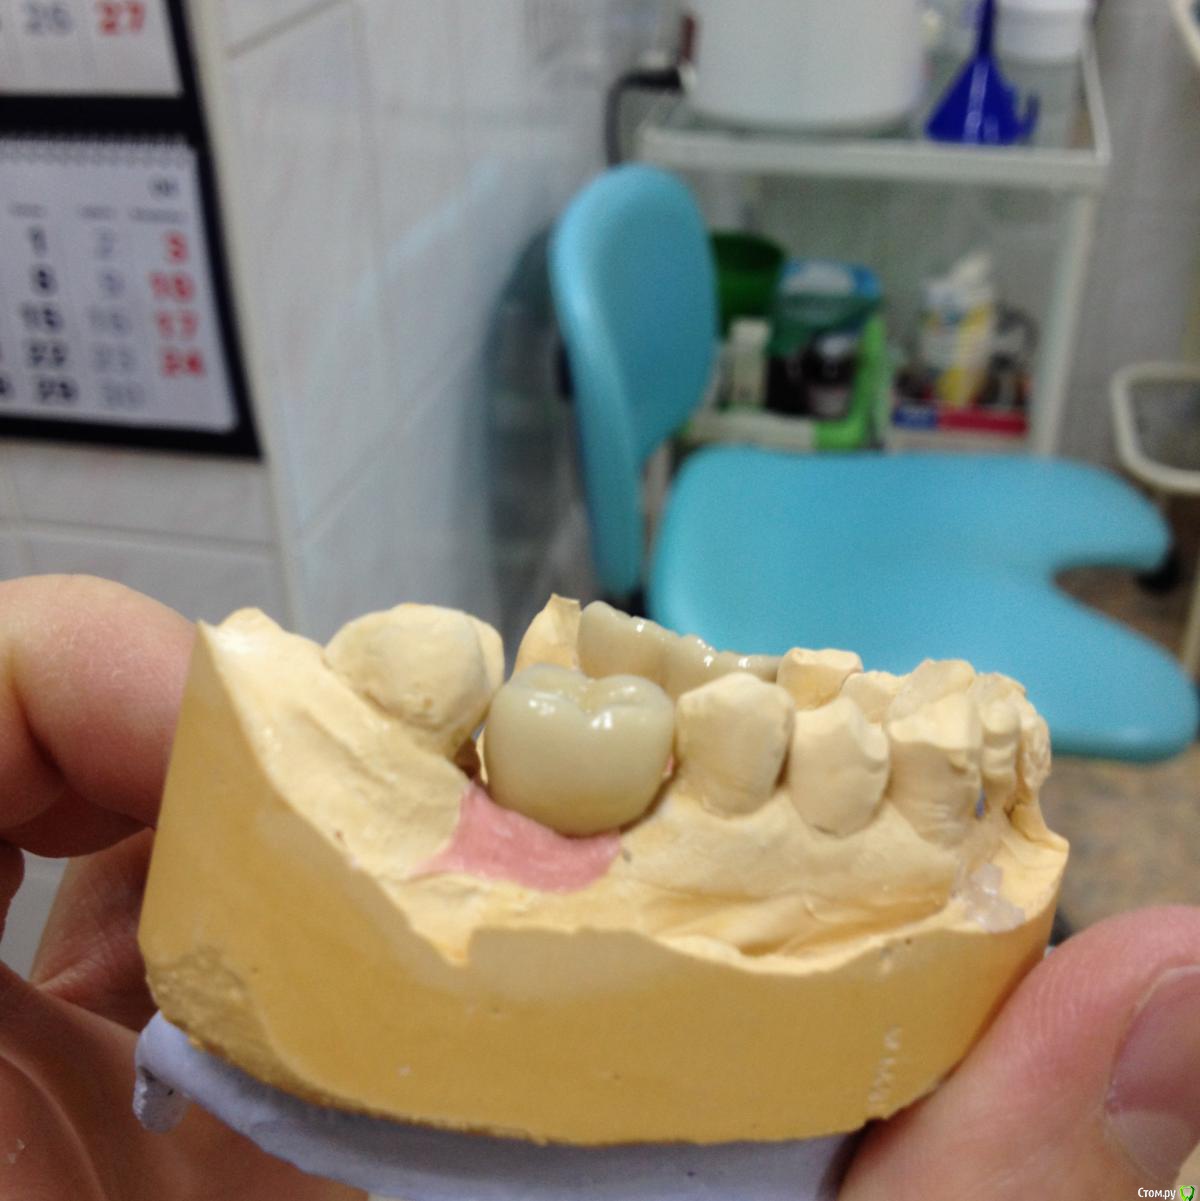

Shakirbura Опубликовано 13 марта, 2016 Поделиться Опубликовано 13 марта, 2016 Здравствуйте, коллеги! Собственно, моя первая работа на имплантатах. Очень хочется услышать мнение опытных врачей, сам еще плохо понимаю где есть ошибки. Сразу оговорюсь, что контакт между 46,45 исправлен.Заранее спасибо! Ссылка на комментарий

alekszander Опубликовано 14 марта, 2016 Поделиться Опубликовано 14 марта, 2016 Для первой работы не плохо, особенно если еще мало чего понимаете. Вопрос - зачем мост в 3-м сегменте? Ссылка на комментарий

Shakirbura Опубликовано 14 марта, 2016 Автор Поделиться Опубликовано 14 марта, 2016 Для первой работы не плохо, особенно если еще мало чего понимаете. Вопрос - зачем мост в 3-м сегменте?Мостом делал с расчетом уменьшить нагрузку. Встали как то не очеь хорошо импланты. Вы бы сделали одиночки в этой ситуации? Ссылка на комментарий

chervoncevdaniil Опубликовано 14 марта, 2016 Поделиться Опубликовано 14 марта, 2016 Мостом делал с расчетом уменьшить нагрузку. Встали как то не очеь хорошо импланты. Вы бы сделали одиночки в этой ситуации?все правильно,что импланты объединили в боковом сегменте Ссылка на комментарий

Freelancer1981 Опубликовано 14 марта, 2016 Поделиться Опубликовано 14 марта, 2016 тем более в такой ситуации обьединение продлит срок службы и вообще в боковых я страюсь почти всегда обьединять. Ссылка на комментарий